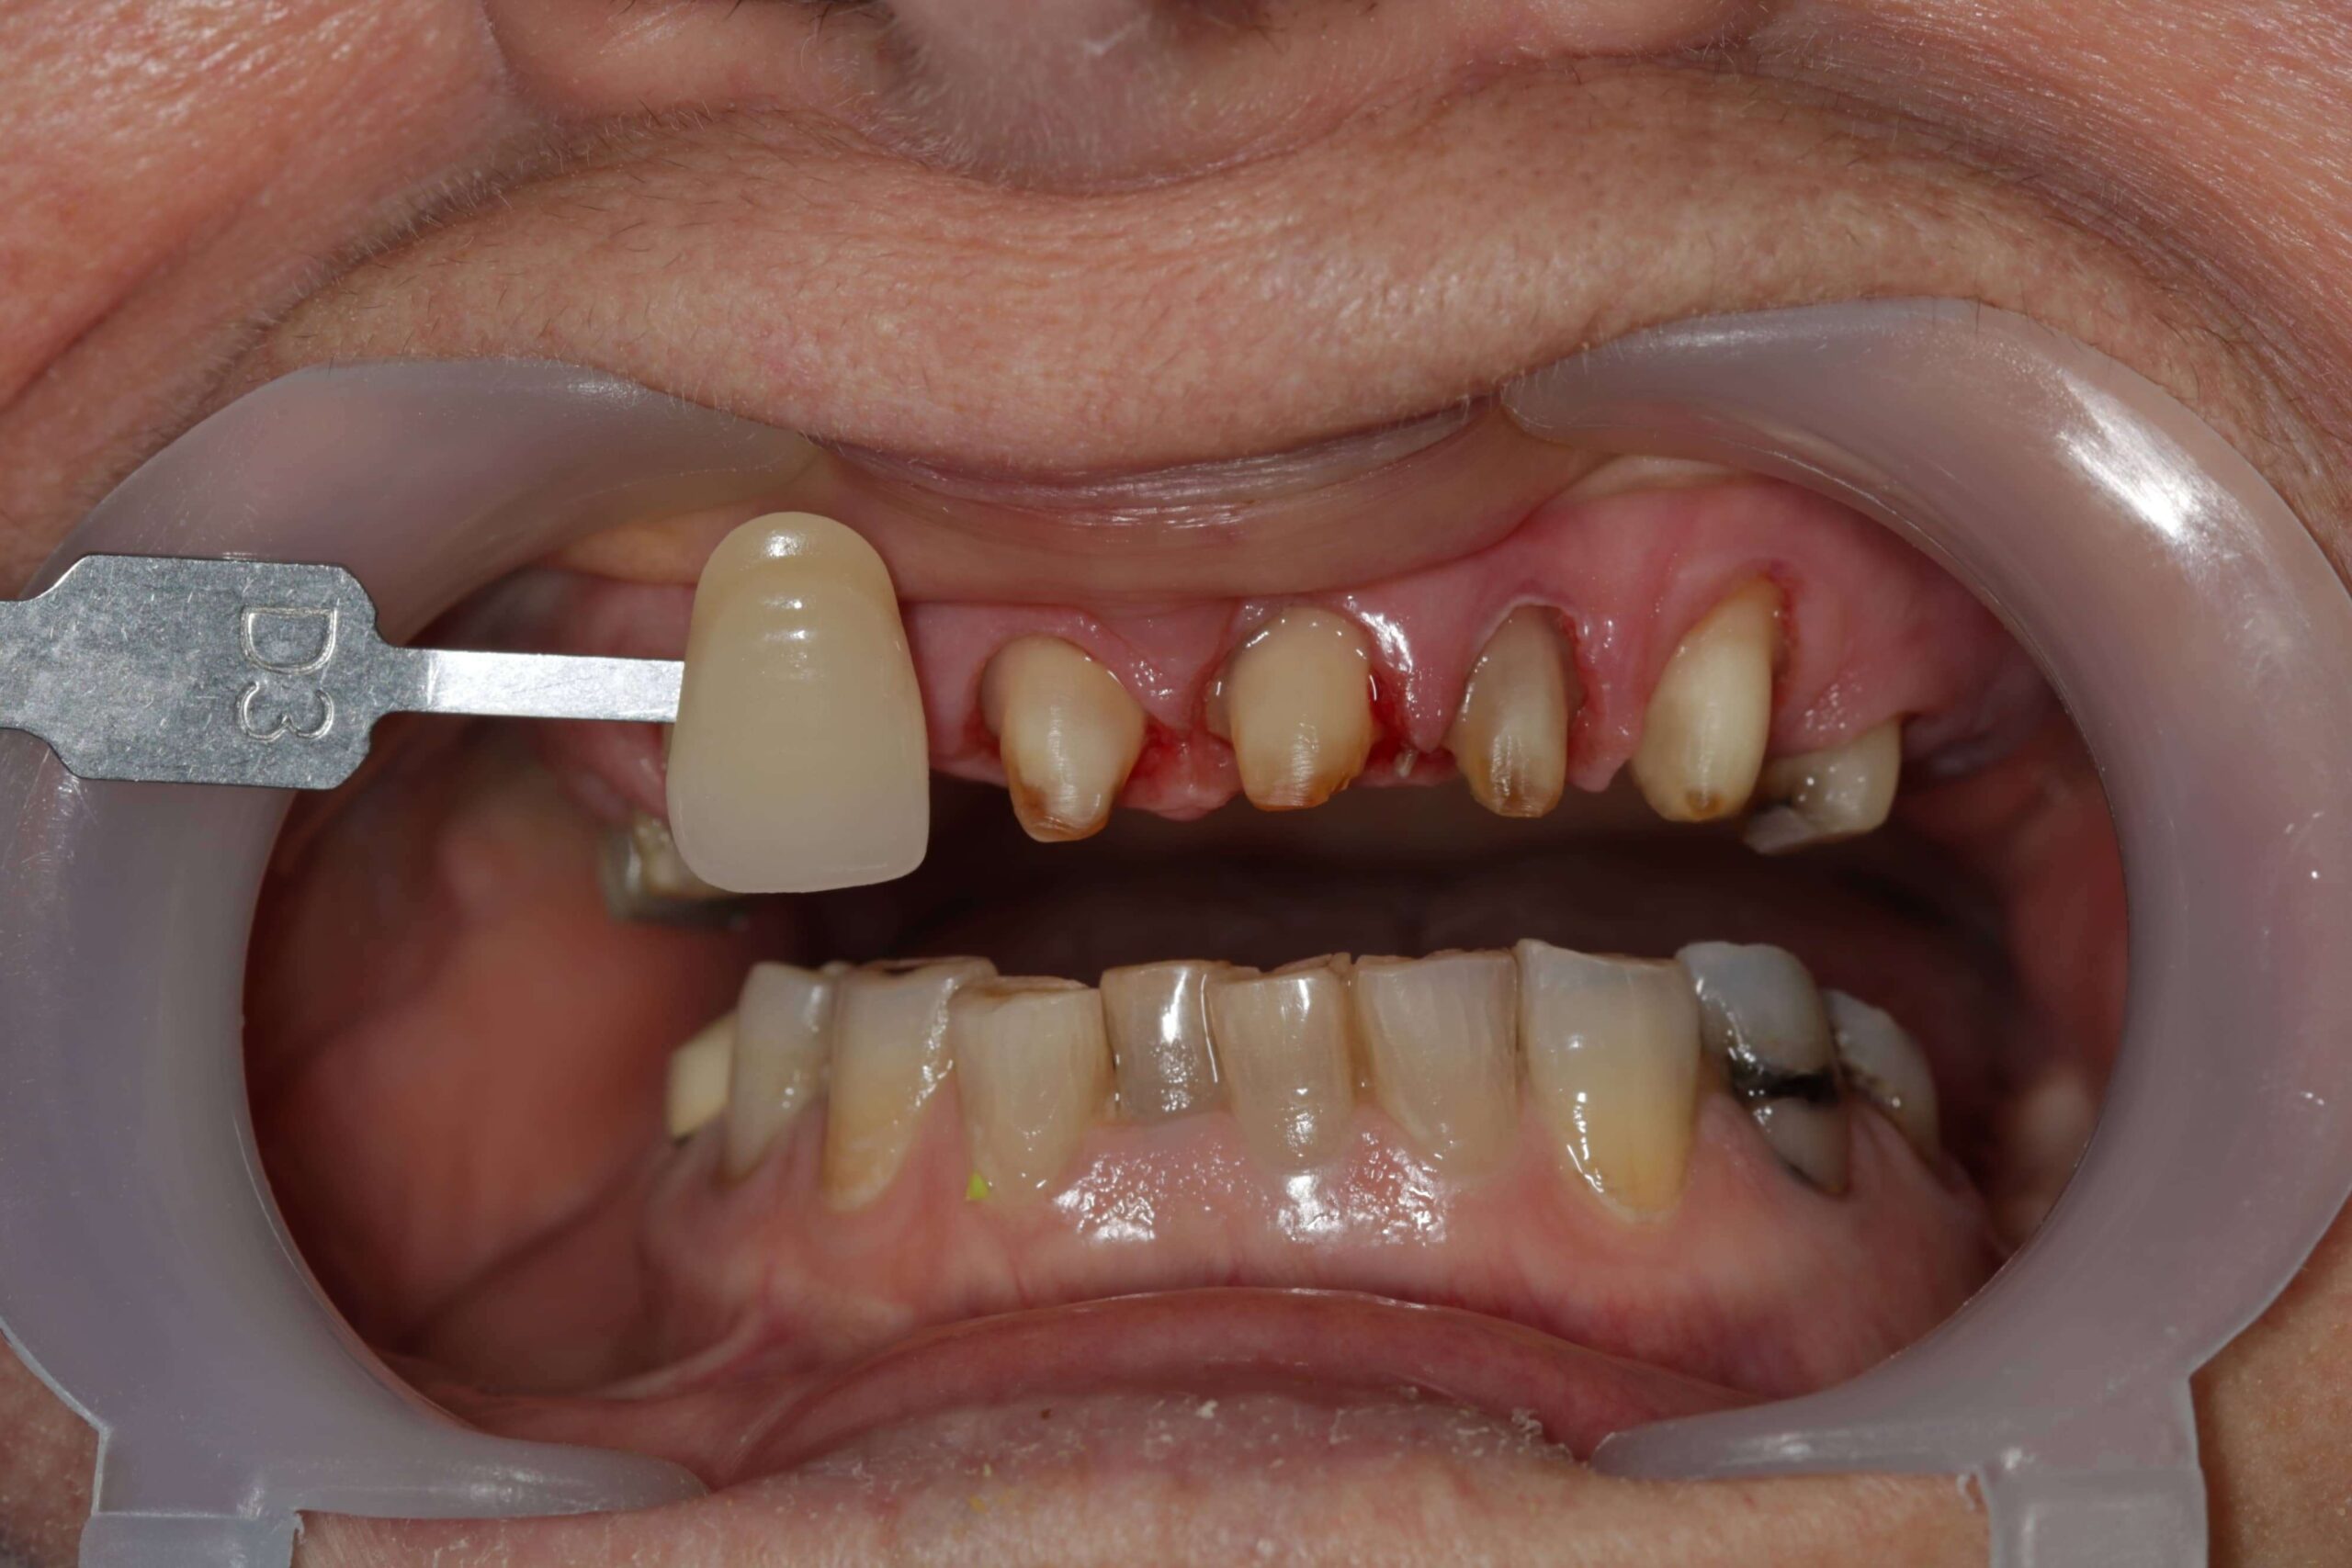

- Nem megfelelően kialakított fogpótlások: rosszul illeszkedő koronák, hidak vagy kivehető pótlások hosszú távon megváltoztathatják a harapási viszonyokat, túlterhelhetik az állkapocsízületet, és funkcionális egyensúlyzavart idézhetnek elő. Ez gyakran vezet feszüléshez, rágás közbeni fájdalomhoz vagy ízületi kattogáshoz.